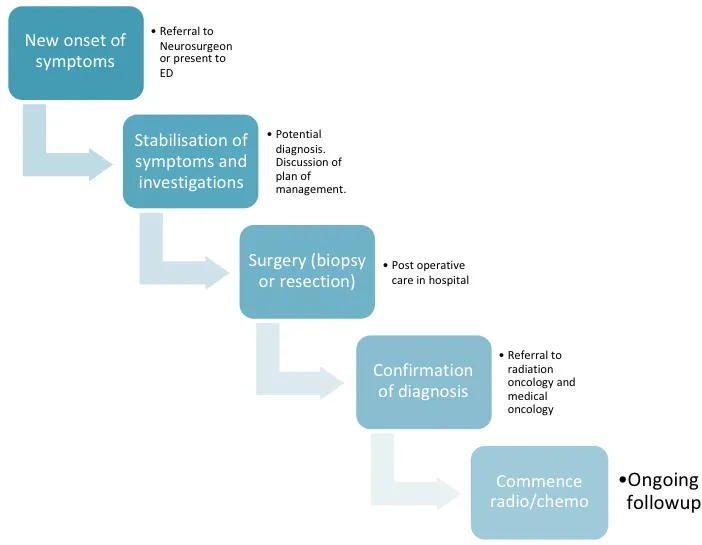

脑癌的发病是基因改变导致细胞异常增殖的结果。这些克隆细胞会形成肿瘤,而原始的变异细胞则会受益于快速生长等优势。由起始细胞产生的细胞将成为肿瘤群体中的优势细胞。这一过程被称为克隆选择,并不会随着肿瘤的发展而停止,从而导致恶性肿瘤的快速生长。以下是患者被诊断出患有脑癌后的情况图:

通常在确诊之前,恶性肿瘤细胞就开始快速增殖,有时甚至会导致不同部位的多种并发症。这就是脑机接口发挥作用的时候了。